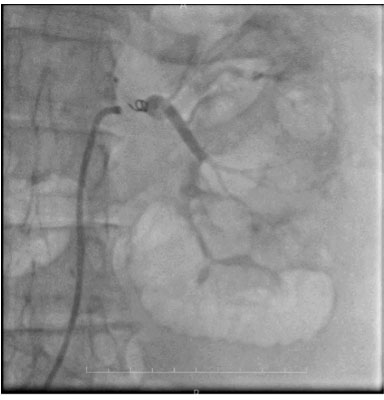

Figure 2: Trans-femoral arteriography showing left renal tumor.

Share Image: